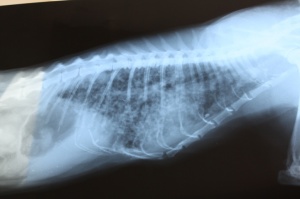

Рентген сегодня показал полное поражение легких - развились метастазы.

Рентген, который мы у тебя нашли, кажется еще я делала - там нет метастаз.

А вот в сравнении: